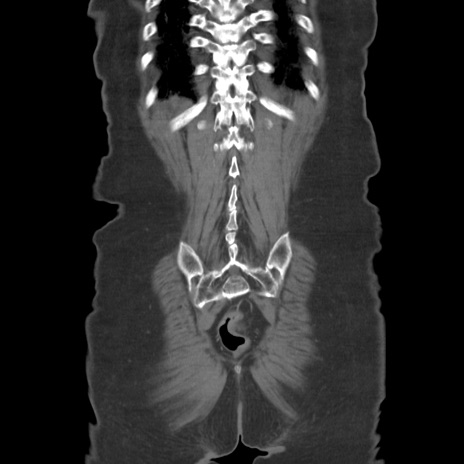

横断像

【症例】80歳代女性

【主訴】下腹部痛

【現病歴】約8時間前より下腹部痛の出現あり、救急外来受診。

【既往歴】両側付属器切除

【身体所見】意識清明、下腹部正中に手術痕あり、その部位に一致して圧痛と反跳痛あり。腸蠕動音は亢進。

【データ】WBC 9300、CRP 0.15